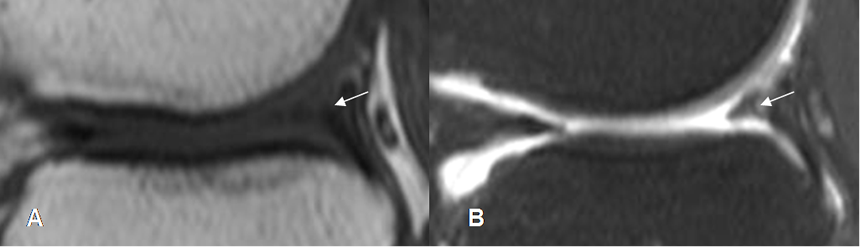

Fig 74. Ruptura meniscal oblicua.

A: RM sagital en T1 y B: RM sagital en STIR. Imagen en sentido oblicuo, que se comunica con la superficie articular inferior, por ruptura meniscal.

Fig 75. Ruptura meniscal radial.

A y B: RM sagital en T1. Alteración en la parte medial del menisco, por ruptura radial.